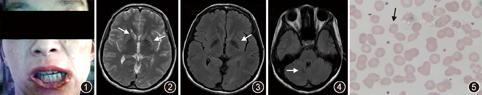

患者女,30岁,因"口唇四肢不自主运动2年,加重3个月余"入院。患者2年前无明显诱因下出现口唇及四肢不自主运动,清醒时明显,入睡后消失;3个月前,患者症状加重,咬伤下唇,进食时将食物外推,并有口齿不清伴行走不稳,当地医院诊断考虑"肌张力障碍?强迫症?",予"氯硝安定"、"帕罗西汀"等治疗后改善不佳,遂至浙江大学医学院附属第二医院就诊。发病以来,患者体重减轻约10 kg。否认毒物接触史。父母为近亲结婚(表兄妹),有1兄,体健。体格检查:消瘦体型,角膜K-F环阴性,下唇变薄破溃,部分缺损,流涎(图1),可见口周不自主运动,口齿欠清,对答尚切题,双侧咽反射减弱,四肢肌张力减低,肌力5级,四肢不自主运动存在,指鼻试验稳准,双上肢反击征阳性,后拉试验阳性,行走时协调性差,双侧肱二头肌腱反射减弱,余腱反射未引出,双侧病理征阴性。

患者表现为突出的口周及四肢不自主运动,流涎,进食时将食物外推,肌酸激酶明显升高,头颅磁共振成像可见尾状核及壳核轻度萎缩(图2,图3,图4),综上,临床考虑神经棘红细胞增多症可能,予查外周血涂片可见棘红细胞,比例约55%(图5),故神经棘红细胞增多症诊断明确。予口服氟哌啶醇1 mg每天2次逐渐加量至2 mg每天2次,并补充维生素E等治疗后,复查肌酸激酶水平下降,症状较前改善,出院后随访12个月患者病情平稳。